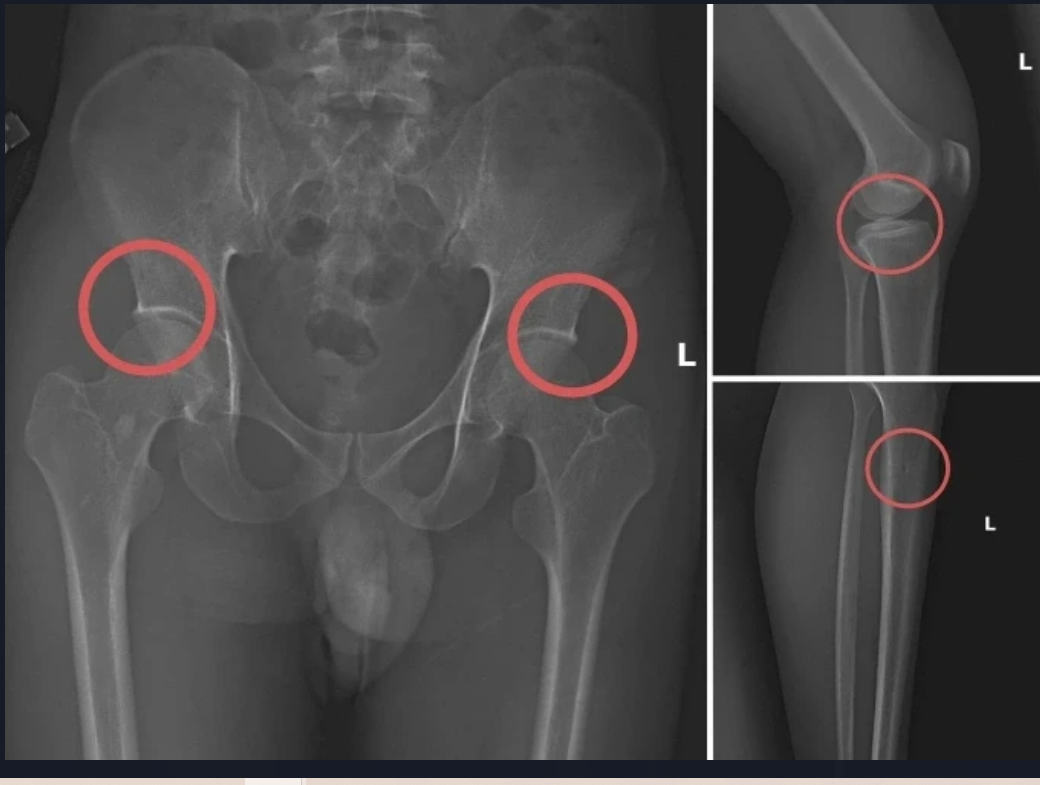

Các vết thương do Châu tự tạo nên. Ảnh: Công an cung cấp

Tại đây, đối tượng Châu tiêm thuốc mê vào tĩnh mạch tay phải của người mua bảo hiểm, sau khoảng 1 phút họ bị mê đi thì Châu sẽ dùng búa và kim tiêm đục, đâm vào vùng cơ thể đã thống nhất từ trước để tạo vết tổn thương trên xương cho nứt, vỡ (thường sẽ làm rạn nứt, vỡ vùng xương chậu, xương đùi…).

Tiếp đó, đối tượng Châu đợi khoảng 10-20 phút khi thuốc mê hết tác dụng, những bệnh nhân tỉnh lại, anh ta hướng dẫn những người này tạo ra những vụ tai nạn tự nhiên để được hưởng bảo hiểm như: Bị điện giật ngã làm nạn nhân gãy xương chậu, đi suối ngã gãy chân... rồi nhờ người đưa đến Trung tâm y tế, bệnh viện khám và điều trị lấy bệnh án.